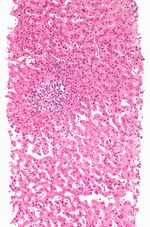

نناقش أدناه الأنماط النسيجية المرضية المحددة لإصابة الكبد من التلف الناجم عن المخدرات.

نخر منطقي

هذا هو النوع الأكثر شيوعًا من نخر خلايا الكبد الناجم عن الأدوية حيث تكون الإصابة محصورة إلى حد كبير في منطقة معينة من فصيص الكبد . قد يظهر على شكل مستوى مرتفع جدًا من ناقلة أمين الألانين واضطراب شديد في وظائف الكبد مما يؤدي إلى فشل الكبد الحاد .

في هذا النمط ، يرتبط نخر الخلايا الكبدية بترشح الخلايا الالتهابية. يمكن أن يكون هناك ثلاثة أنواع من التهاب الكبد الناجم عن الأدوية. (أ) التهاب الكبد الفيروسي هو الأكثر شيوعًا ، حيث تتشابه السمات النسيجية مع التهاب الكبد الفيروسي الحاد. (ب) في التهاب الكبد البؤري أو غير النوعي ، قد تصاحب البؤر المتناثرة لنخر الخلية تسلل الخلايا اللمفاوية . (ج) التهاب الكبد المزمن يشبه إلى حد بعيد التهاب الكبد المناعي سريرياً ومصليًا ونسيجيًا.